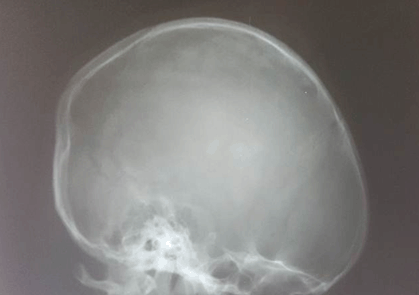

Complete blood count revealed hematocrit of 28%, total white cell count of 275x109/L and platelets count of 980x109/L. Peripheral blood film (PBF) revealed all spectrum of white blood cells (Figure 3) –myeloblast 3%, promyelocytes 6%, myelocytes 40%, metamyelocytes 12%, band form 19% and neutrophil 20%. Bone marrow aspiration (BMA) cytology showed markedly increased myelopoiesis, the myelogram showed evidence of sequential maturation along the cell line with a peak at the myelocyte stage and myeloblast count of less than 5%. The PBF and BMA were in keeping with CML in chronic phase; rtPCR analysis of whole blood was positive for Philadelphia chromosome and the b3a2 transcript type (classical CML) was detected; quantification revealed BCR-ABL quantity of 4,578 copies per 2.5 micro liter of cDNA, ABL copies of 931,750 per 2.5 ml of cDNA and BCR-ABL/ABL ratio of 0.49%. The serum biochemistry was unremarkable. A skull X-ray revealed no bony involvement by the scalp swelling (Figure 4). Cerebrospinal fluid analysis was negative for malignant cells. Chest X-ray revealed cardiomegaly with right upper lobe opacity. Two-dimensional echocardiogram was performed and showed severe left ventricular dysfunction and dilated left ventricular wall, with increased pulmonary vascular resistance.

Figure 4: Normal skull X-ray which indicates no obvious bony involvement from the scalp mass.